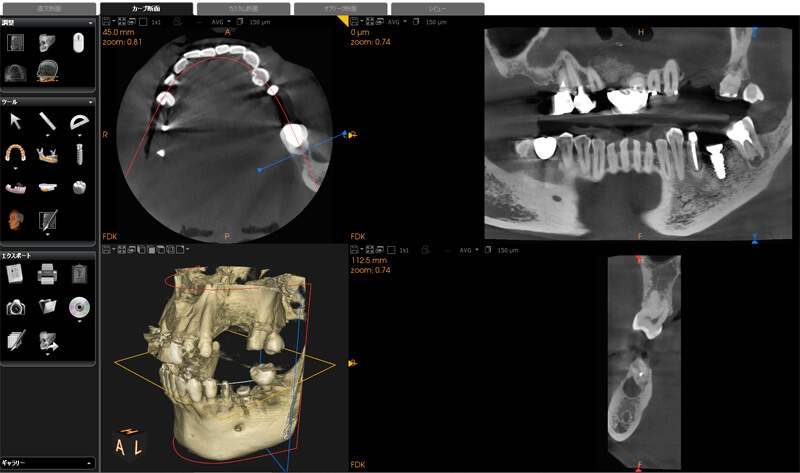

一般に行われているレントゲン検査でもある程度の情報を得ることができますが、立体的に存在している歯と周りの組織を2次元のレントゲンフィルム上で診断するには、情報量に限界があります。

当院では術前に、必要に応じて歯科用CTを用いて3次元的な情報を得ることで正確な診査診断を行っております。病気の発見はもとより、病変(炎症によって骨がとけている部分など)の大きさ、進行状態や歯根の形態も精密に診査してから治療を行っています。こうした術前の診査診断によって、あらかじめ治療ができるかできないか(状況によっては残念ながら抜歯になってしまうケースもあります)を診断し、できるだけ最小限の歯の切削量で治療を行うことができます。